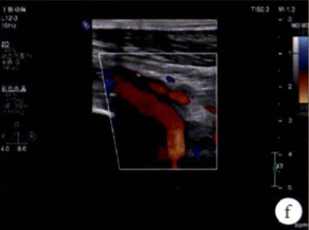

图:f)经吸栓、球囊扩张等治疗措施后腘动脉血流图像